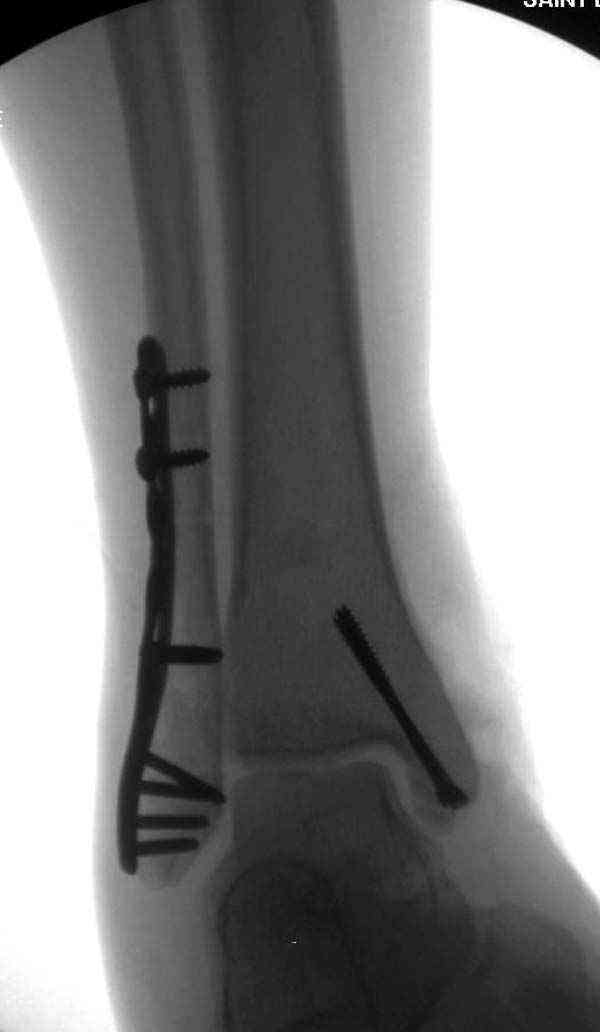

Случай прошлого года:пациентка-молодая ,крупная женщина ,30лет.Травма в начале апреля 2009г-пронационный перелом лодыжек с подвывихом стопы.Ко мне обратилась через 35 дней,прооперирована 22.05.2009г.Внутренняя лодыжка фиксирована по Веберу,наружная реконструктивной пластиной с наложением болта-стяжки.Иммобилизация "сапожок" в течении месяца,затем пригипсовано "стремя".Гипс снят 10.07.2009г

Достаточно быстрое восстановление функции.В октябре 2009г-почувствовала боль,в области рубца над гайкой открылся свищ.На Р-граммах-консолидация переломов и смещение гайки по стяжке.10.11.2009г-конструкции удалены,санация,заживление ран.В настоящее время пациентку ничего не беспокоит.На операции-раскручивание гайки-болталась на конце стяжки.Вопросы:какой механизм раскручивания и что я неправильно сделал?Свои версии:1)в области синдесмоза успела образоваться рубцовая ткань,которая при движении в суставе"пружинила",поскольку голеностопный сустав является спиральным, то и биомеханика подобна кривошипному механизму.2)Реконструктивная пластина не "реконструировалась" по форме лодыжки.Наложил,как есть.То есть подпружинивала сама пластина.Ну,это мои догадки.Что нужно,чтобы избегать впредь таких,пусть и не "страшных"осложнений:Рассверливать через лодыжку область синдесмоза?Ставить шайбу-гровер?Тщательно моделировать пластину?Прилагаю сравнительные снимки-сразу после операции и перед удалением конструкции.

Создаётся впечатление,что болт-стяжка не раскрутился, он не дотянут изначально, и просто мигрировал с течением времени, под действием циклических нагрузок, в латеральную сторону, образовал пролежень и перфорировал кожу. И подвывих не до конца установленным болтом-стяжкой устранён не полностью. Это, что можно сказать по представленным снимкам. А пластину особенно в этой локализации всё таки необходимо моделировать особенно тщательно, я вообще зачастую устанавливаю её по задней поверхности, естественно с моделированием.

Закрутил со скрипом,(ну,я ,что кого -то обманывал,что не верите),а пролежней никаких не видел,пластину "отковыривал".Хотя,мысль такая перед удалением пластины была.

Визуально никаких вопросов по репозиции не было.Да и на основании чего сомнения,что наружная лодыжка не полностью репонирована или прорезалась проволка ???Я не вижу...Снимок после репозиции справа.

Раз ,есть желание посмотреть другую проекцию выкладываю-ну лучшего качества нет...